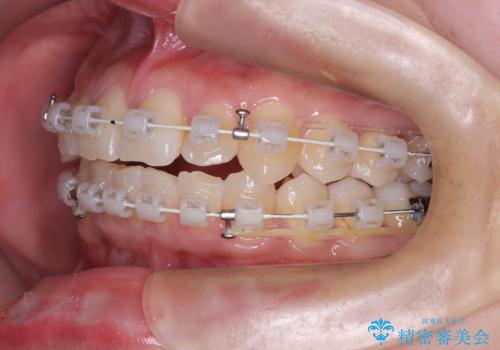

- 矯正装置

- 審美ワイヤー

- 患者様は、前歯の重なり(叢生)が気になるとのことでご来院されました。診断の結果、奥歯を後方に移動することで前歯にスペースを確保し、非抜歯で歯列を整える方針としました。治療には審美性の高いホワイトワイヤーを使用し、奥歯の遠心移動にはリンガルアーチを装着しました。治療期間は約2年を予定し、月に一度の調整を通じて歯の動きを細かく管理しました。

非抜歯矯正は、歯を抜かずに自然な歯列を作るため、歯列全体のバランスを考慮する必要があります。本症例では、リンガルアーチによる奥歯の遠心移動を用いましたが、初期段階で軽い違和感を覚える方もいらっしゃいます。そのため、装置装着後のケアや食生活について詳しく説明を行い、患者様にも協力いただきました。また、審美ワイヤーを使用することで、日常生活での見た目のストレスを軽減し、治療を快適に進めることができました。